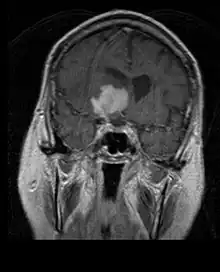

La tomodensitométrie (TDM) et L'imagerie par résonance magnétique (IRM) peuvent détecter efficacement une néoplasie dans le cerveau. L'IRM est plus sensible que la TDM pour identifier les lésions, mais présente des contre- indications pour les patients porteurs de stimulateurs cardiaques, de prothèses incompatibles, de clips métalliques et contre-indications. La TDM reste la méthode de choix pour détecter les calcifications au sein des lésions ou les érosions osseuses de la calotte ou de base du crâne. L'utilisation d' agents de contraste, iodés dans le cas du scanner et paramagnétiques (gadolinium) dans le cas de l'IRM, permet l'acquisition d'informations sur la vascularisation et l'intégrité de la barrière hémato-encéphalique, une meilleure définition de la tumeur tumorale par rapport à l' œdème environnant et à la génération d' hypothèses sur le degré de malignité. L'examen radiologique permet également d'évaluer les effets mécaniques et les modifications importantes des structures cérébrales résultant de la tumeur, telles que l' hydrocéphalie et les hernies, dont les effets peuvent être fatals. Enfin, en préparation à la chirurgie, ce diagnostic peut être utilisé pour déterminer la localisation de la lésion ou l'infiltration de la tumeur dans des zones vitales du cerveau. À cette fin, l'IRM est plus efficace que la tomodensitométrie car elle peut fournir des images en trois dimensions.

Sur-L'IRM montre une tumeur intracrânienne comme une lésion massive qui peut devenir plus luminescente après utilisation du produit de contraste. Cependant, il y a toujours une anomalie de signal dans -L'imagerie par résonance magnétique, qui indique la présence d'une néoplasie ou d'un œdème vasogénique. Habituellement, une luminescence accrue (amélioration du contraste) indique une tumeur d'un grade supérieur de malignité. Un anneau de contraste est caractéristique du glioblastome, avec la partie luminescente correspondant à la partie vitale de la tumeur maligne, et la plus foncée - zone hypointense correspondant à une nécrose tissulaire.

Glioblastome

Les tumeurs des cellules gliales les plus courantes et les plus malignes sont les glioblastomes. Ils consistent en une masse hétérogène de cellules d'astrocytome peu différenciées principalement chez l'adulte. Ils surviennent généralement dans les hémisphères cérébraux, plus rarement dans le tronc cérébral ou la moelle épinière. Sauf dans de très rares cas, comme toutes les tumeurs cérébrales, elles ne s'étendent pas au-delà des structures du système nerveux central.

Le glioblastome peut provenir d'une forme diffuse (II. grade) ou un astrocytome anaplasique (III. grade) développer. Dans ce dernier cas, il est dit secondaire. Cependant, lorsqu'elle survient sans antécédent ni signe de malignité antérieure, on parle de maladie primaire. Les glioblastomes sont traités par chirurgie, radiothérapie et chimiothérapie. Ils sont difficiles à guérir et rares sont les cas qui survivent au-delà de trois ans.

Les métastases cérébrales sont les néoplasmes intracrâniens les plus courants chez les adultes, étant dix fois plus fréquents que les tumeurs cérébrales primaires. Ils marchent à 20 jusqu'à 40 pour cent des adultes atteints de cancer et sont principalement associés au cancer du poumon et du sein et au mélanome . Ces lésions résultent de la propagation des cellules cancéreuses dans la circulation sanguine et surviennent le plus souvent à la jonction de la matière grise et blanche, où la section transversale des vaisseaux sanguins change, emprisonnant les embolies de cellules tumorales . 80 % des lésions surviennent dans les hémisphères cérébraux, 15 pour cent dans le cervelet et 5 pour cent dans le tronc cérébral. Environ 80 % des patients ont des antécédents de cancer systémique et 70 pour cent ont de multiples métastases cérébrales.